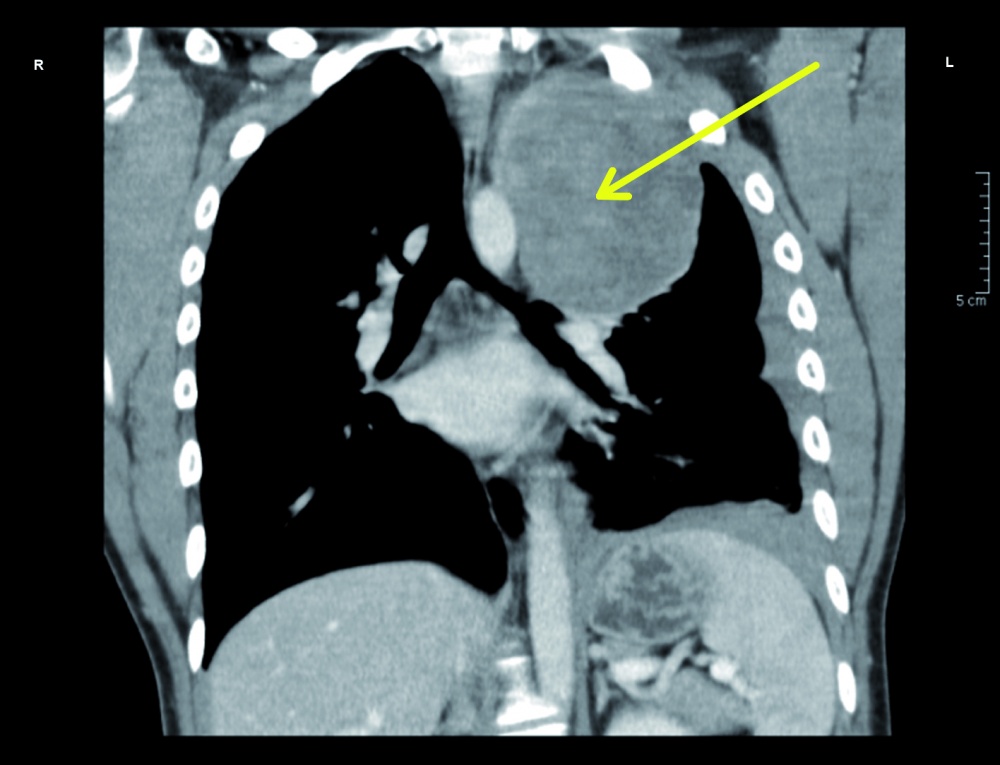

In der Nacht stellte sich ein 25-jähriger Mann in der zentralen interdisziplinären Notaufnahme des Bundeswehrkrankenhauses (BwKrhs) Ulm vor. Er war aus einer nahegelegenen Klinik aufgrund von atemabhängigen linkseitigen Thoraxschmerzen mit unklarem röntgenologischen Befund zugewiesen worden. Bei der Anamnese berichtete der Patient, dass er wenige Stunden vor der ersten Arztvorstellung beim Sport einen plötzlichen linksseitigen thorakalen Schmerz verspürt habe. Dieser sei persistent, atemabhängig und wurde von ihm mit einer Intensität von 8 (numerische visuelle Analogskala von 0 – 10) beschrieben. In einer Computertomographie des Thorax (diese wurde ohne Kontrastmittel als Trauma-CT durchgeführt, da zu diesem Zeitpunkt zunächst kein Verdacht auf das Vorliegen einer Tumorerkrankung bestand) war eine hypervaskularisierte Raumforderung von 9 x 9 x 11 cm im linken Oberlappen zu sehen. Ebenso wurde bei dieser Untersuchung der dringliche Verdacht auf einen Hämatothorax geäußert. Aufgrund einer möglicherweise erforderlichen thoraxchirurgischen Intervention mit gegebenenfalls notwendiger konsekutiver intensivmedizinischer Betreuung wurde der Patient zu uns verlegt.

Zwei Tage nach Aufnahme zeigte der Patient einen starken Hämoglobinabfall von 12,4 g/dl auf 7,9 g/dl, so dass eine notfallmäßige Thorakoskopie zur Blutstillung und Histologiegewinnung durchgeführt werden musste. Auf eine erneute Bildgebung präoperativ wurde hierbei aufgrund eines symptomatischen Patienten mit Kurzatmigkeit und niedrigem Hämoglobinwert verzichtet. Bei dem Eingriff bestätigte sich der initiale Verdacht eines Hämatothorax. Es konnten 1,5 l teils frischen, teils mit Koageln durchsetzten Blutes abgesaugt werden. Es zeigte sich links apikal ein von der dorsalen Thoraxwand ausgehender und dort adhärenter Tumor mit erkennbarem Tumorstiel, von welchem die Blutung ausging. Aufgrund der thorakoskopisch schlechten Zugänglichkeit der Blutung und der Kontaktfläche zur Thoraxwand wurde eine Thorakotomie durchgeführt, die Blutung gestillt und der Tumor in toto entfernt.